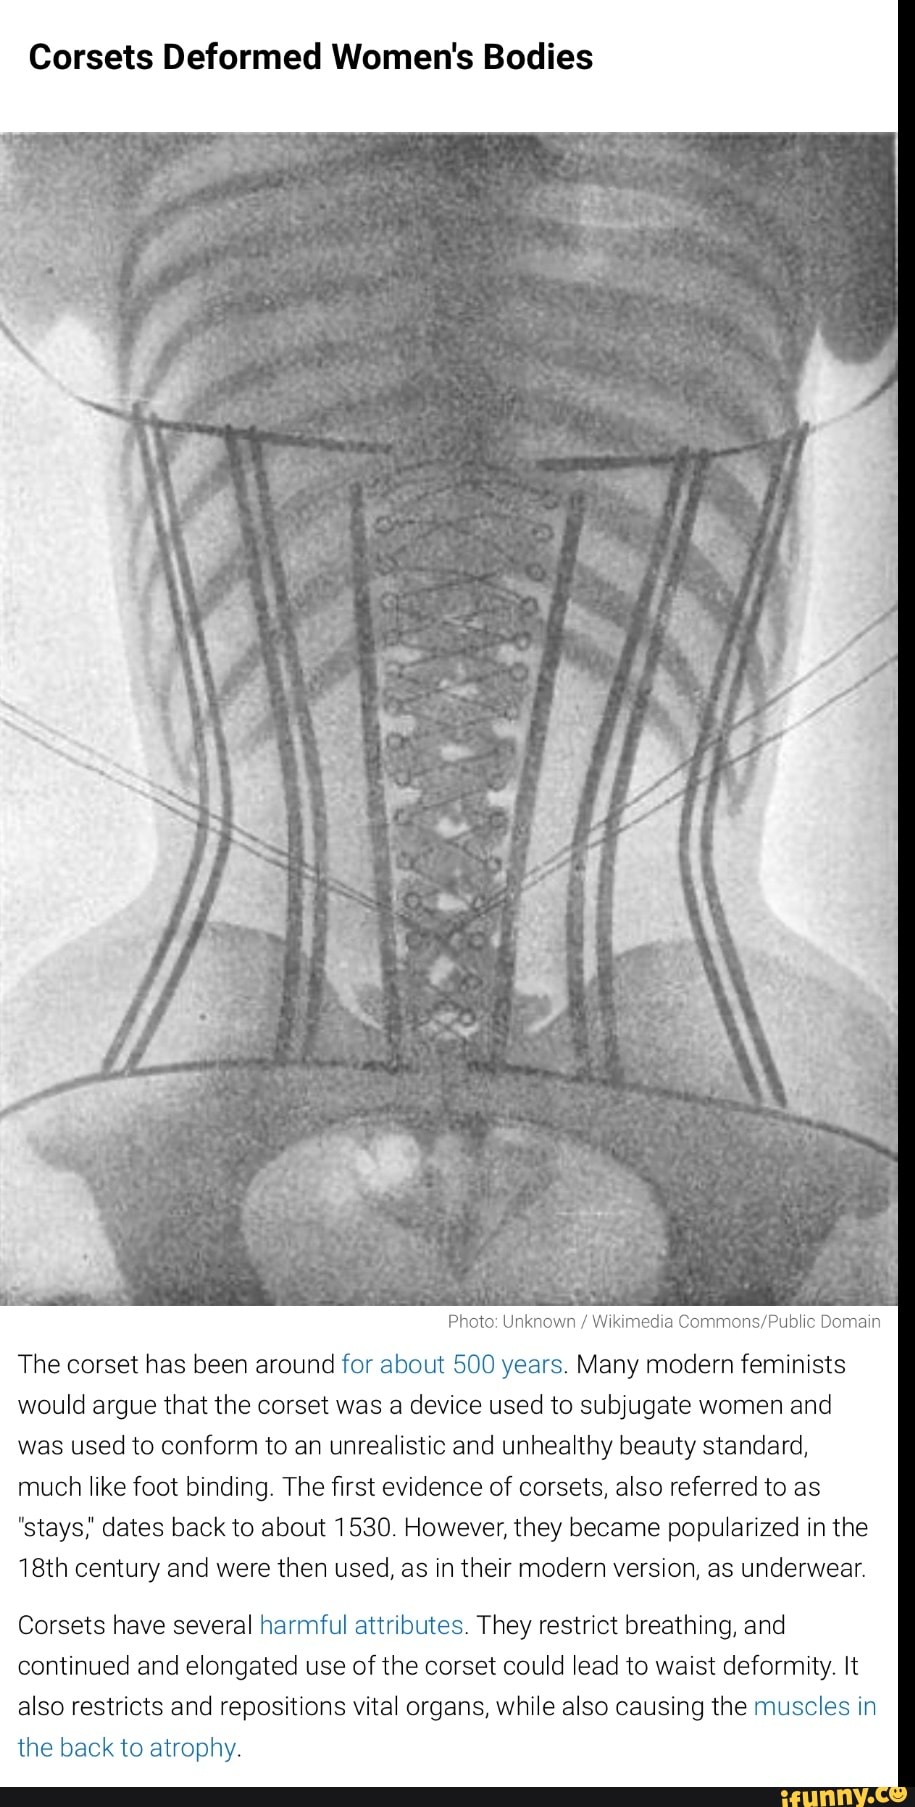

Corsets Deformed Women's Bodies Photo Unkno\ Nikimedia Domain The Are Corsets Unhealthy The pressure placed on the. Many health problems once blamed on the corset are now clearly not the fault of the undergarment. In reality, they never left. Some women have actually passed out from wearing one for too long, says christopher ochner, ph.d., weight loss and. We take a look at some of the most common misconceptions about corsets, corset. Are Corsets Unhealthy.